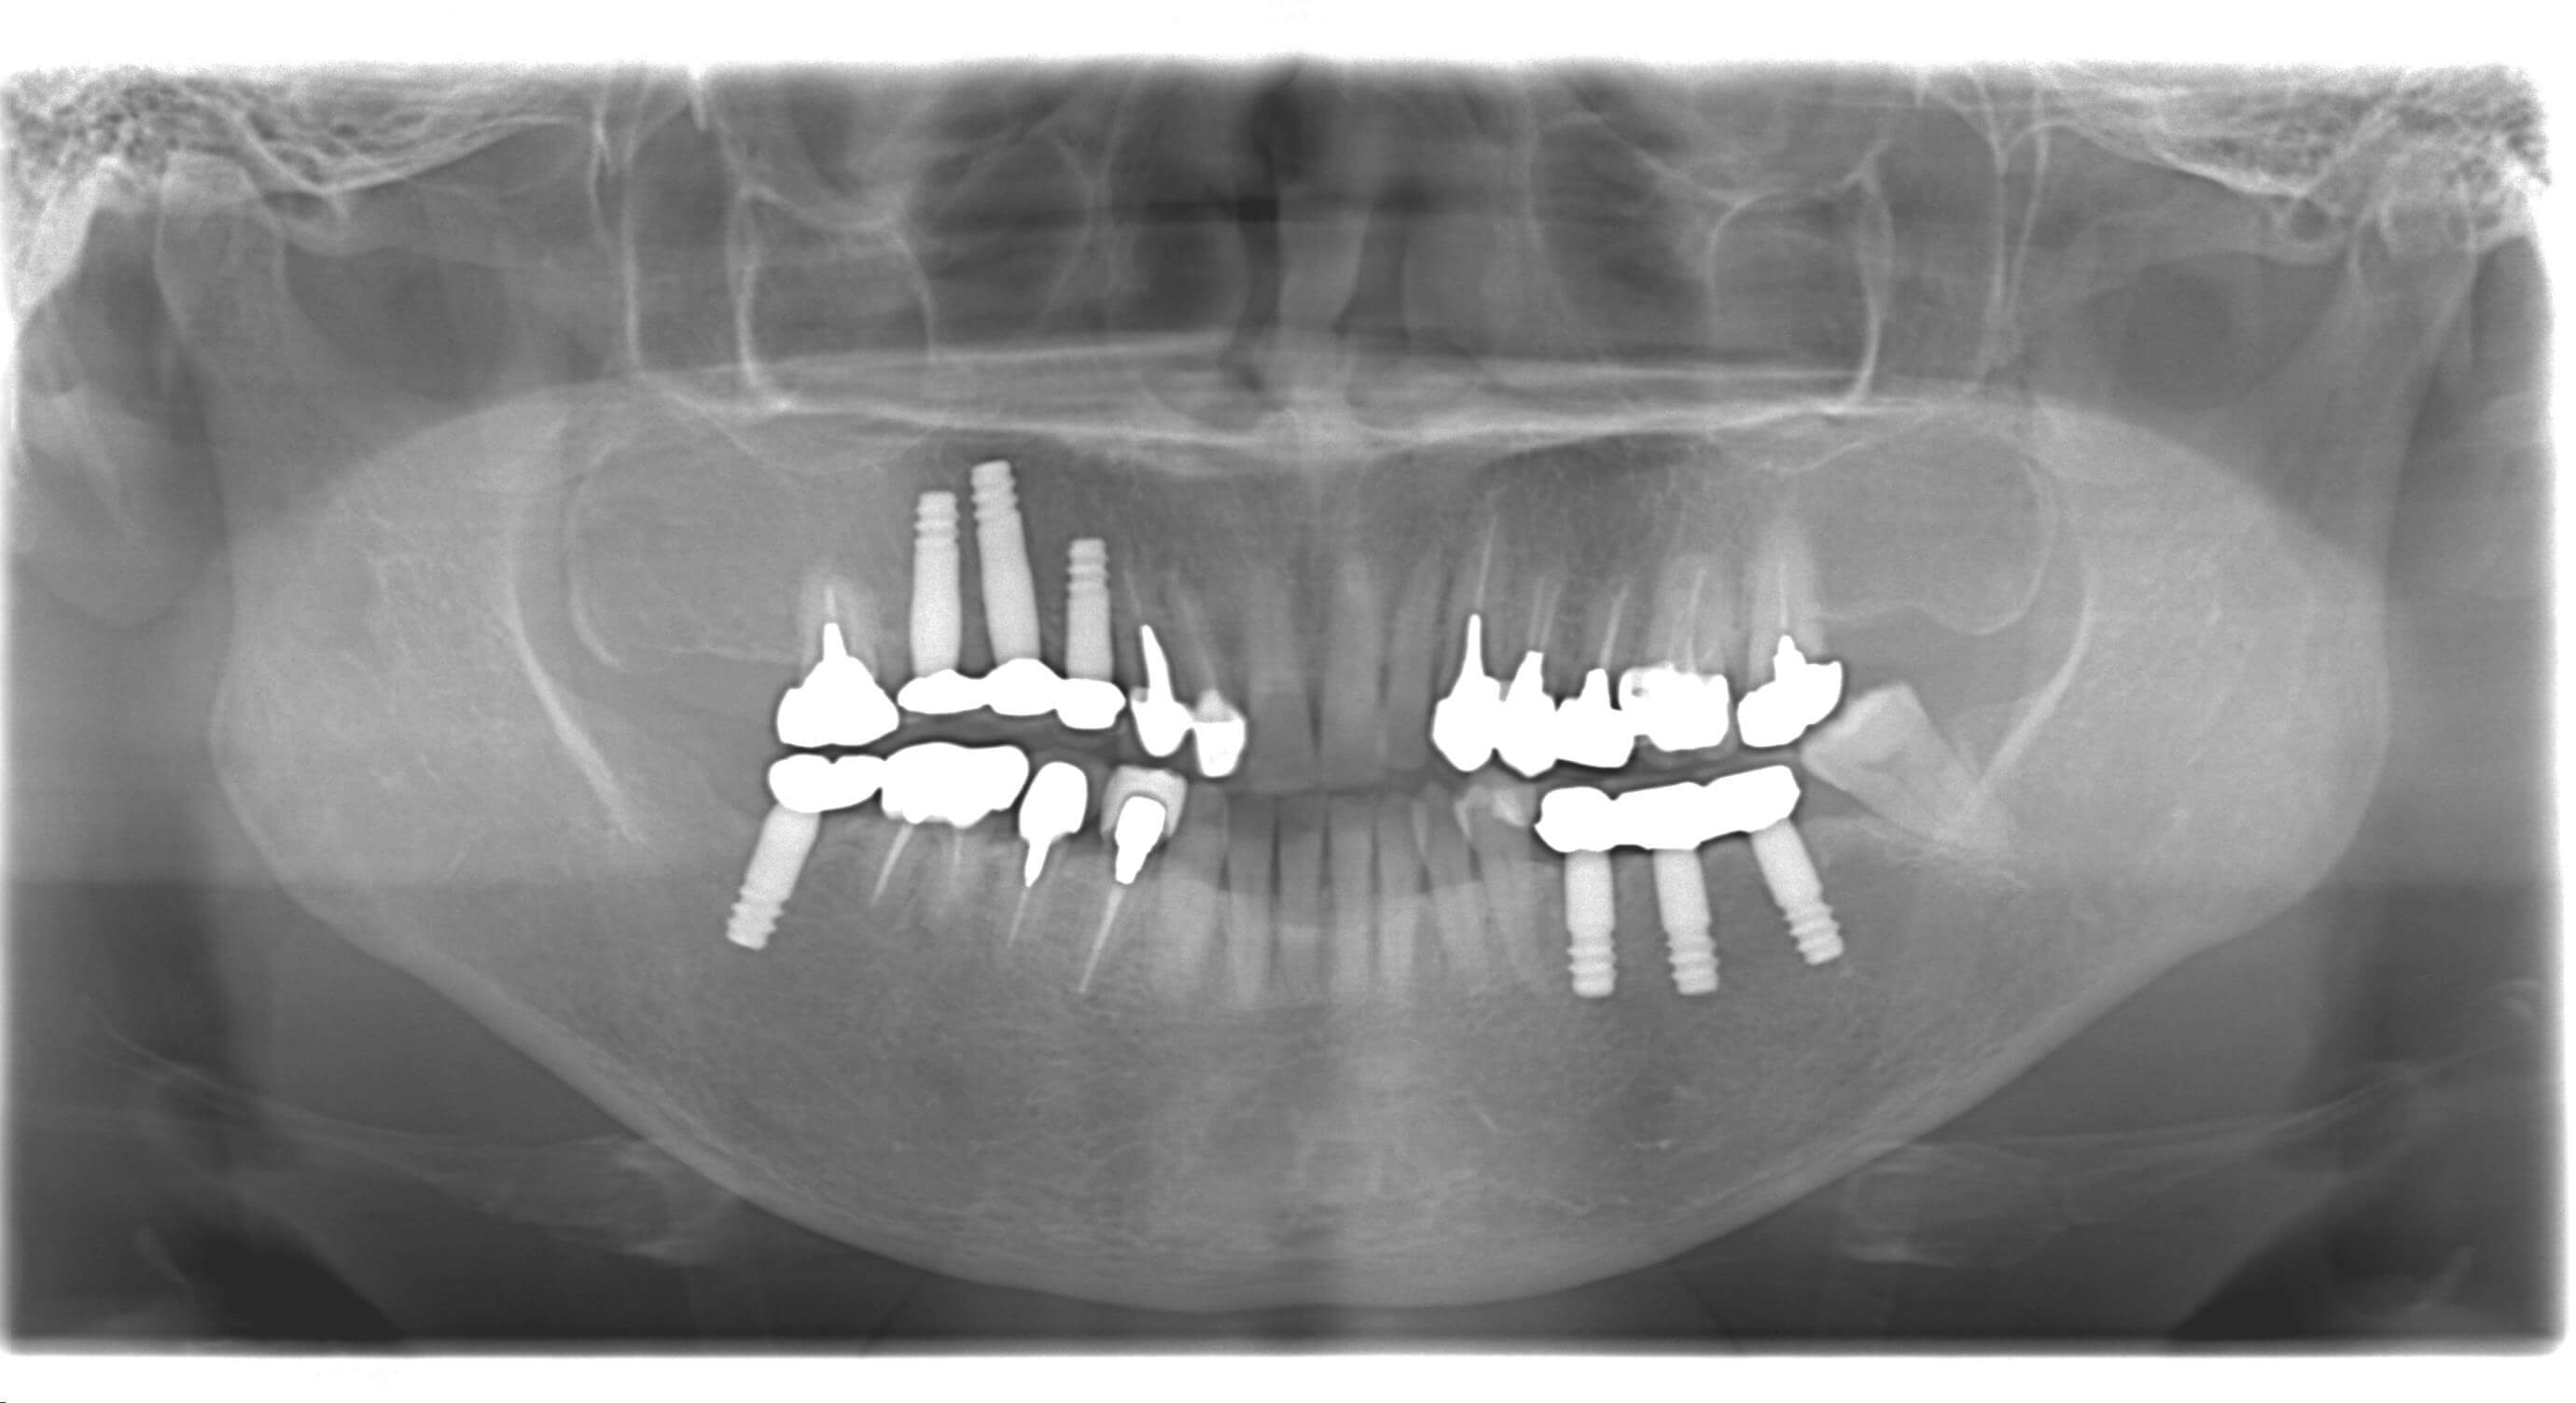

術前診査では、CT及びパノラマレントゲンの撮影、既往歴、健康状態、お口の状況を確認して、必要なインプラントの本数、被せ物を装着するまでのおよその期間、治療費用について治療計画を立案し、患者様に適した治療方法を提案させていただきます。

インプラント後の差し歯ビフォーアフター